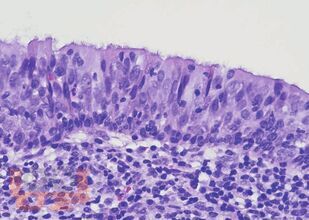

Настоящее руководство-атлас посвящено патоморфологической диагностике опухолей полости носа и носоглотки. Несомненным достоинством книги является систематизированное, лаконичное и вместе с тем весьма информативное изложение текстового материала (клинико-эпидемиологическая картина, морфологическая характеристика, дифференциально-диагностический ряд, необходимые дополнительные методы исследования), а также более 170 цветных микрофотографий наблюдений из собственной клинической практики с подробными подписями. Наряду с опухолями в книге представлен раздел наиболее часто встречающихся неопухолевых процессов синоназального тракта, необходимых для дифференциального диагноза.

Руководство-атлас предлагает структурированный подход с унифицированным изложением современных данных о клинических и морфологических особенностях доброкачественных и злокачественных опухолей носа и носоглотки.